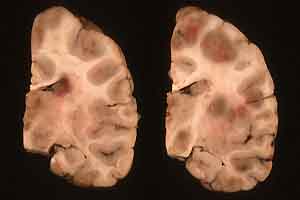

- Gross Pathology: The brain was mildly swollen in the

calvarium. As depicted in the representative 2x2 slide of formalin-fixed

sections, there were many (>10) random areas of soft purple

discoloration, both in the cortices and brain stem. These spanned

gyri and were easily depressed. Some were partially liquefied

with petechiae and ecchymoses rimming foci in the basal ganglia

and thalamus. There was brown mucus in a bronchus, suggesting

aspiration with subpleural purple foci, but no palpable consolidation.

- Case 15-1. Multifocally within the cerebral cortex

and brain stem there are areas of brownish-pink discoloration.